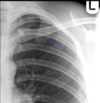

20

Lingular pneumonia

-Infection of the lingula causes the left heart border to become obscured, as shown opposite.